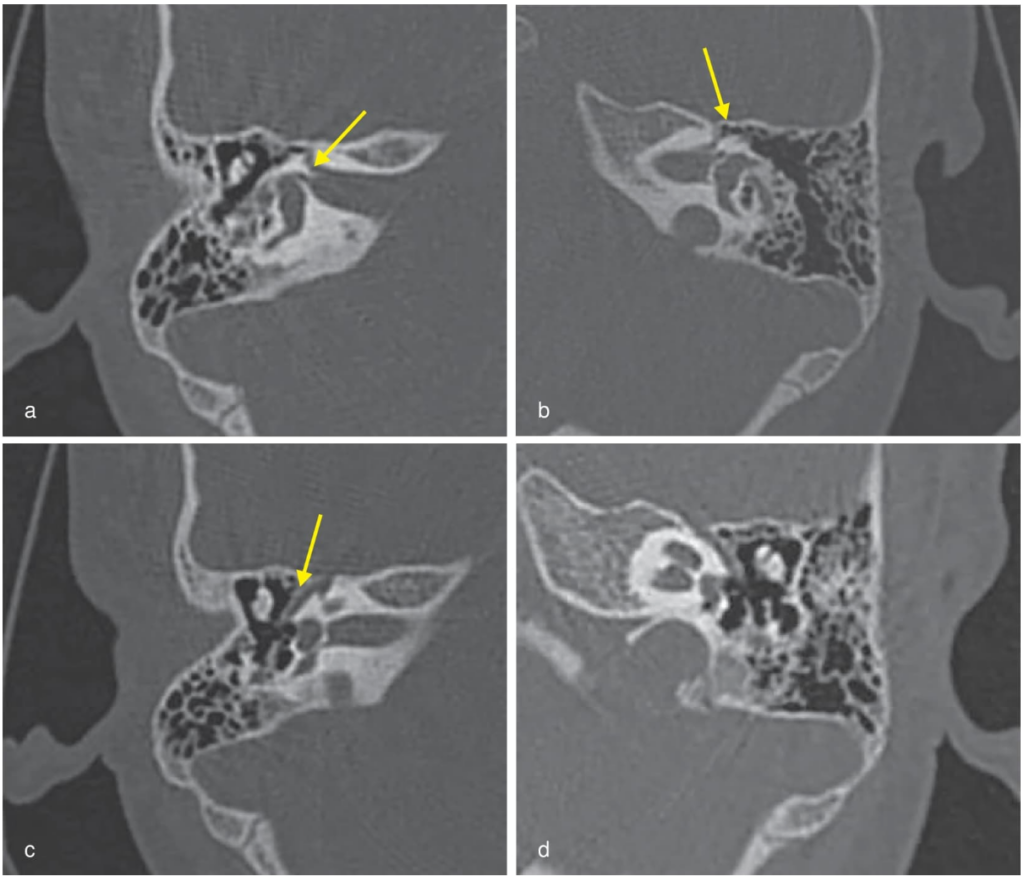

Entre las causas más comunes se encuentra la fractura postraumática bilateral del hueso temporal, generalmente asociada a accidentes de tráfico. Le siguen la parálisis de Bell bilateral, el síndrome de Ramsay Hunt y otras patologías menos frecuentes.

Una niña de 4 años consultó por pérdida completa de las expresiones faciales con un mes de evolución. Los síntomas comenzaron de forma insidiosa con debilidad facial derecha, seguida de desviación del ángulo de la boca, cierre ocular incompleto y, posteriormente, compromiso bilateral completo. No existían antecedentes infecciosos, traumáticos ni quirúrgicos relevantes.

En la exploración clínica, la paciente presentaba un rostro inexpresivo, cierre ocular bilateral incompleto y ausencia de movimientos faciales voluntarios. Se diagnosticó una parálisis facial bilateral de grado VI (neurona motora inferior). Los estudios complementarios, incluidos análisis de laboratorio, tomografía computarizada y resonancia magnética, no mostraron hallazgos patológicos relevantes.